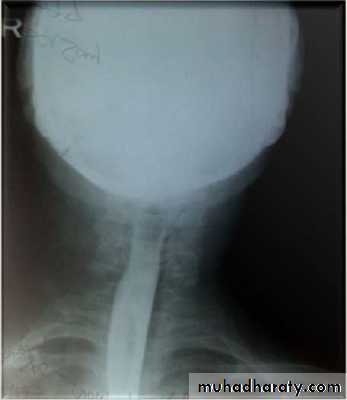

Barium swallow findings:

Tapered narrowing of the lower esophagus, esophageal body is dilated, aperistaltic and food-filled.Clinical features:

Chest X-ray: widening of the mediastinum, aspiration pneumonia.A barium swallow: tapered narrowing of the lower esophagus, esophageal body is dilated, aperistaltic and food-filled.